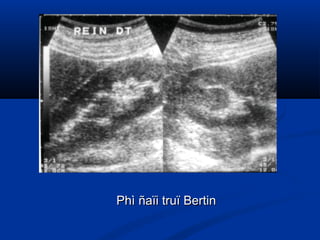

Phì ñaïi truï BertinPhì ñaïi truï Bertin

Truï BertinTruï Bertin